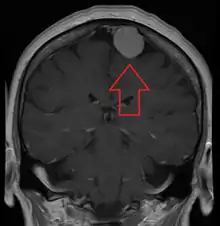

| A contrast-enhanced CT scan of the brain, demonstrating the appearance of a meningioma | |

Meningiomas are visualized readily with contrast CT, MRI with gadolinium,[22] and arteriography, all attributed to the fact that meningiomas are extra-axial and vascularized. CSF protein levels are usually found to be elevated when lumbar puncture is used to obtain spinal fluid. On T1-weighted contrast-enhanced MRI, they may show a typical dural tail sign absent in some rare forms of meningiomas.[17]